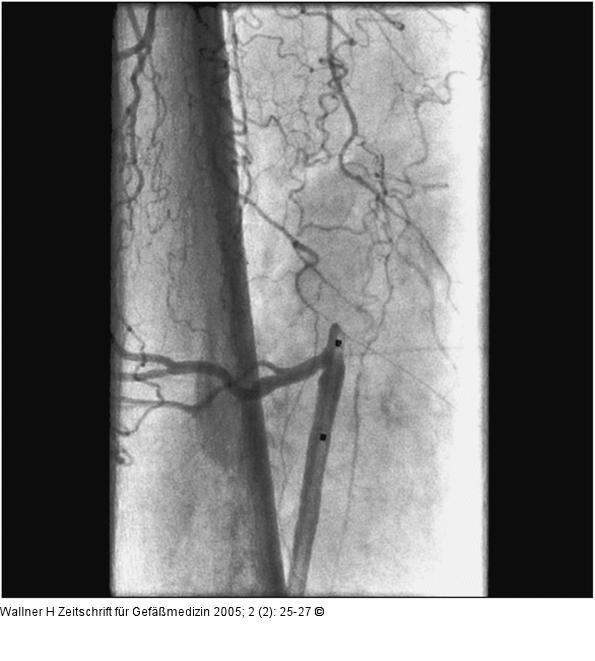

Abbildung 4: Backup-Ballon

Liegende Schleuse, Marker des Backup-Ballons (Patient in Bauchlage) |